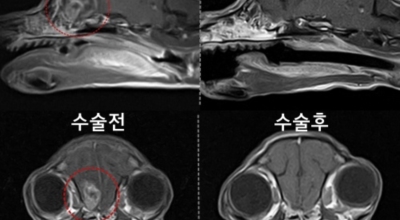

뇌종양이 악성인 경우, 빨리 자라는 특성이 있기 때문에 수술적으로 절제가 필요할 수 있습니다. 하지만 수술로 종양이 완벽하게 제거가 어려운 경우, 수술 후에 방사선 치료와 항암치료를 추가적으로 시행되어요. 요즘 들어서 뇌조직의 훼손을 최소화하고 수술 흉터가 거의 남지 않는 방법으로 하는 치료인 감마나이프 방사선 수술이 있답니다. 이 방사선 수술은 전신 마취와 피부 절개가 필요 없으며, 합병증이나 후유증이 적은 것으로 알려져 있답니다.

종양의 부위가 너무 커서 다른 방법을 활용하기 어렵거나 신경학적으로 생기는 증상이 너무 심하다고 판단이 될 경우에 활용할 수 있답니다. 하지만 다발성 병변으로 발생한 종양이거나 면역력이 많이 떨어져 있는 등 전신이 쇠약한 환자의 경우, 신중하게 생각해보아야 해요.